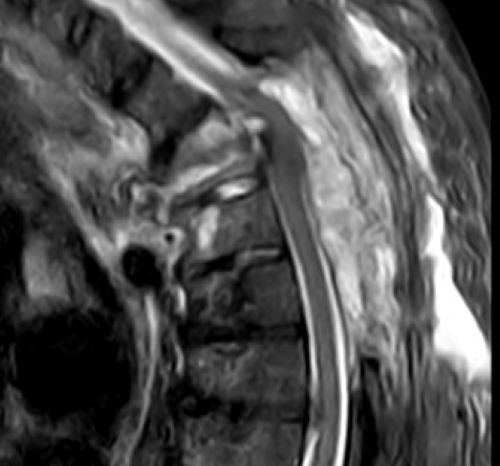

Bei einer Wirbelsäule MRT können sowohl knöcherne Strukturen als auch Weichteile erkannt und folglich untersucht werden. Dadurch eignet sich die MRT Wirbelsäule besonders gut, um Schmerzen mit unklarer Ursache im Rücken und der Wirbelsäule abzuklären. Denn auf den MRT-Bildern des Rückens können Schäden an der Wirbelsäule, den Bandscheiben und am Rückenmark erfasst werden.

Mögliche Erkrankungen an diesen Strukturen sind mit der nicht-invasiven bildgebenden Methode, wie es die Kernspintomographie bzw. Magnetresonanztomographie ist, bereits in frühen Stadien erkennbar, was für viele Patienten die Aussichten auf eine erfolgreiche Therapie erhöht bzw. die Prognose verbessert.

Auch komplexe Krankheiten wie Multiple Sklerose können mit Hilfe einer MRT zuverlässig diagnostiziert werden.